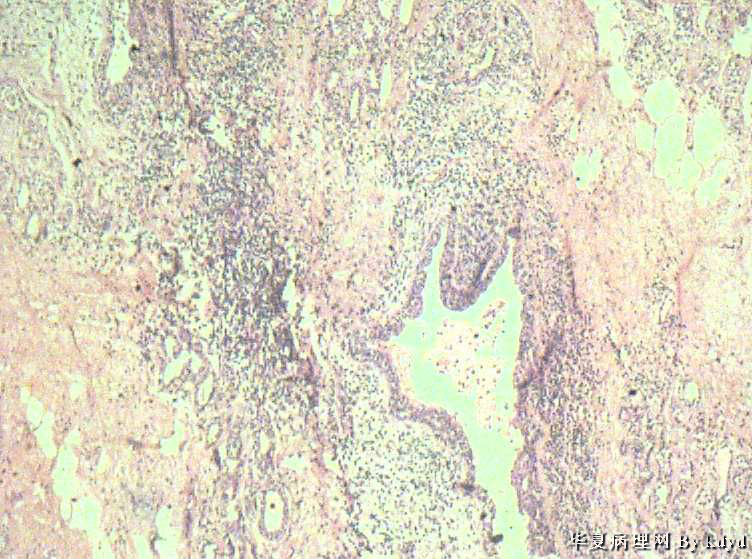

B3997左乳肿瘤--浸润性导管癌?

37岁,女。左侧乳腺肿块发现5个多月,伴隐痛。

手术见:肿块与周围组织分界不清,无明显包膜。

大体:不整形组织大小约3.5*35*2CM,未见明显包膜。质较软,切面浅黄色,一侧见一小囊腔直径约0.8CM囊壁较粗糙。

标签:乳腺浸润性导管癌 原位癌

浸润性乳腺导管癌?

乳腺浸润性导管癌

应该是个浸润性导管癌

但是,片子质量欠佳

不太敢直接下

诊断乳腺浸润性导管癌确实有些担心,制片质量确实要提高,制作优良的切片,是正确诊断的前提。

囊壁内大量炎细胞浸润,囊壁被覆细胞有明显异型,可见核分裂,考虑癌,不知有无陷阱